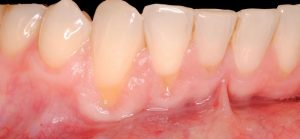

Compartimos con vosotros un nuevo caso de recesiones múltiples de encías, solucionado con éxito en nuestro centro de salud y estética dental.

Exploración inicial: